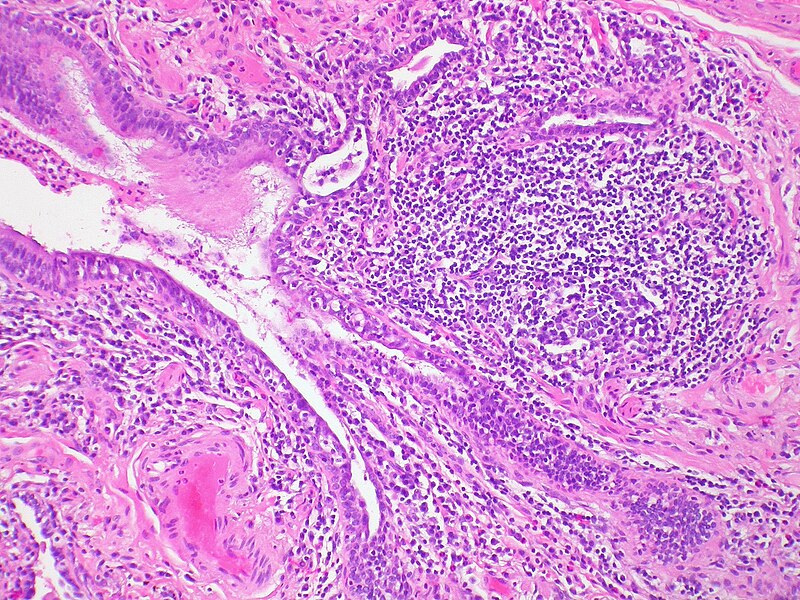

Arthritic changes – Arthritis is related to a condition of painful joints due to inflammation or swelling. A type of arthritis is rheumatoid arthritis, it is an autoimmune disease where the immune system attacks the joints, starting with the lining of joints. Rheumatoid arthritis is heavily related to lung problems, about 80% of arthritic patients have lung-related issues, making it the second leading cause of death with rheumatoid arthritis patients. Rheumatoid arthritis caused lung problems are most commonly extra-articular i.e., outside of the joints and involves pulmonary nodules; damage to the lung airways, pleural effusion and interstitial lung disease. In rheumatoid arthritis associated interstitial lung disease the auto-immune system gets over active and attacks the lungs and causes scarring. With time, the scarring build-up leads to difficulty breathing and reduced lung function.